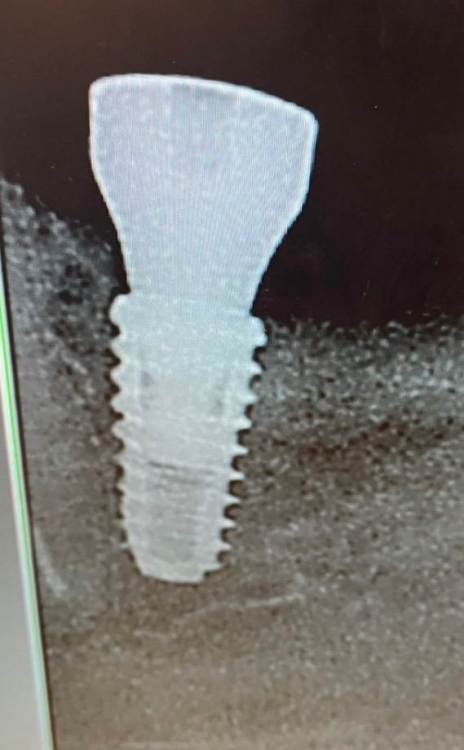

Доктор Кирилл Опубликовано 7 сентября, 2022 Поделиться Опубликовано 7 сентября, 2022 Коллеги, нужна помощь, вот так получилось с установкой импланта. Прошло 10 дней, пациента беспокоит чувствительность при накусывание на соседний зуб. Со слов пациента «как будто двигается, иногда нет, иногда ощущаю» . Что делать? Ссылка на комментарий

TIGER Опубликовано 7 сентября, 2022 Поделиться Опубликовано 7 сентября, 2022 @Доктор Кирилл наблюдать,по снимку не критичная близость 4 Ссылка на комментарий

Fin Опубликовано 7 сентября, 2022 Поделиться Опубликовано 7 сентября, 2022 4 часа назад, Доктор Кирилл сказал: Спасибо! Коллеги, есть ещё мнения? РГ в других проекциях(может быть наложение из-за проекции),имплант оставить 1 Ссылка на комментарий

Pavel-Pskov Опубликовано 9 сентября, 2022 Поделиться Опубликовано 9 сентября, 2022 Вроде по снимку зуб депульпирован, я бы тоже понаблюдал. Ссылка на комментарий